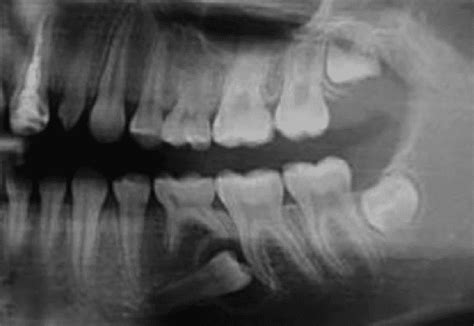

Aunque un médico experimentado puede identificar muchos quistes mediante una simple inspección física y palpación, en ocasiones se requieren pruebas adicionales para confirmar el diagnóstico y asegurar que no se trata de otra patología. Las herramientas de diagnóstico incluyen ecografías, resonancias magnéticas o tomografías computarizadas. En casos donde existe duda sobre el contenido, el médico puede realizar una biopsia o aspiración con aguja fina.